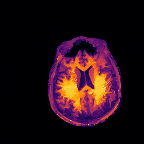

Multi-modality (or multi-channel) imaging is becoming increasingly important and more widely available, e.g. hyperspectral imaging in remote sensing, spectral CT in material sciences as well as multi-contrast MRI and PET-MR in medicine. Research in the last decades resulted in a plethora of mathematical methods to combine data from several modalities. State-of-the-art methods, often formulated as variational regularization, have shown to significantly improve image reconstruction both quantitatively and qualitatively. Almost all of these models rely on the assumption that the modalities are perfectly registered, which is not the case in most real world applications. We propose a variational framework which jointly performs reconstruction and registration, thereby overcoming this hurdle. Numerical results on simulated and real data show the potential of the proposed strategy for various applications in multi-contrast MRI, PET-MR, and hyperspectral imaging: typical misalignments between modalities such as rotations, translations, zooms can be effectively corrected during the reconstruction process. Therefore the proposed framework allows the robust exploitation of shared information across multiple modalities under real conditions.

翻译:多模式(或多通道)成像越来越重要,而且越来越普及,例如遥感中的超光谱成像、材料科学中的光谱CT以及医学中的多调MRI和PET-MR等,过去几十年的研究产生了大量数学方法,将多种模式的数据结合起来。通常作为变异性正规化的先进方法表明,在数量和质量上都大大改进了图像重建。几乎所有这些模型都基于这样一种假设,即模式已经完全登记,而在大多数现实世界应用中情况并非如此。我们提议了一个变通框架,共同进行重建和登记,从而克服这一障碍。模拟和实际数据的数字结果显示,拟议的多调MRI、PET-MR和超光谱成像的各种应用战略具有潜力:在重建过程中可以有效地纠正诸如轮换、翻译、缩影等模式之间的典型的不匹配。因此,拟议的框架允许在现实条件下,在多种模式中大力利用共享的信息。